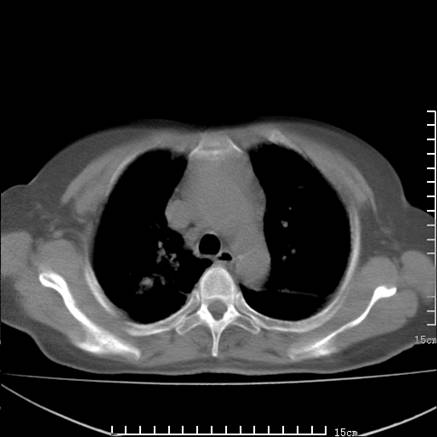

女,王某,58岁,咳嗽三个月余,基层医院二个月前诊为肺结核,用抗结核药二个月无明显疗效。

心包积液致肺瘀血.右侧周围型肺癌伴肺内转移,中间裂积液,叶间胸膜肥厚.右上肺大泡,右侧胸膜肥厚.

双肺继发型tb,心功能不全并肺淤血、心包、双侧叶间裂积液,肺大泡,右下胸膜肥厚钙化。